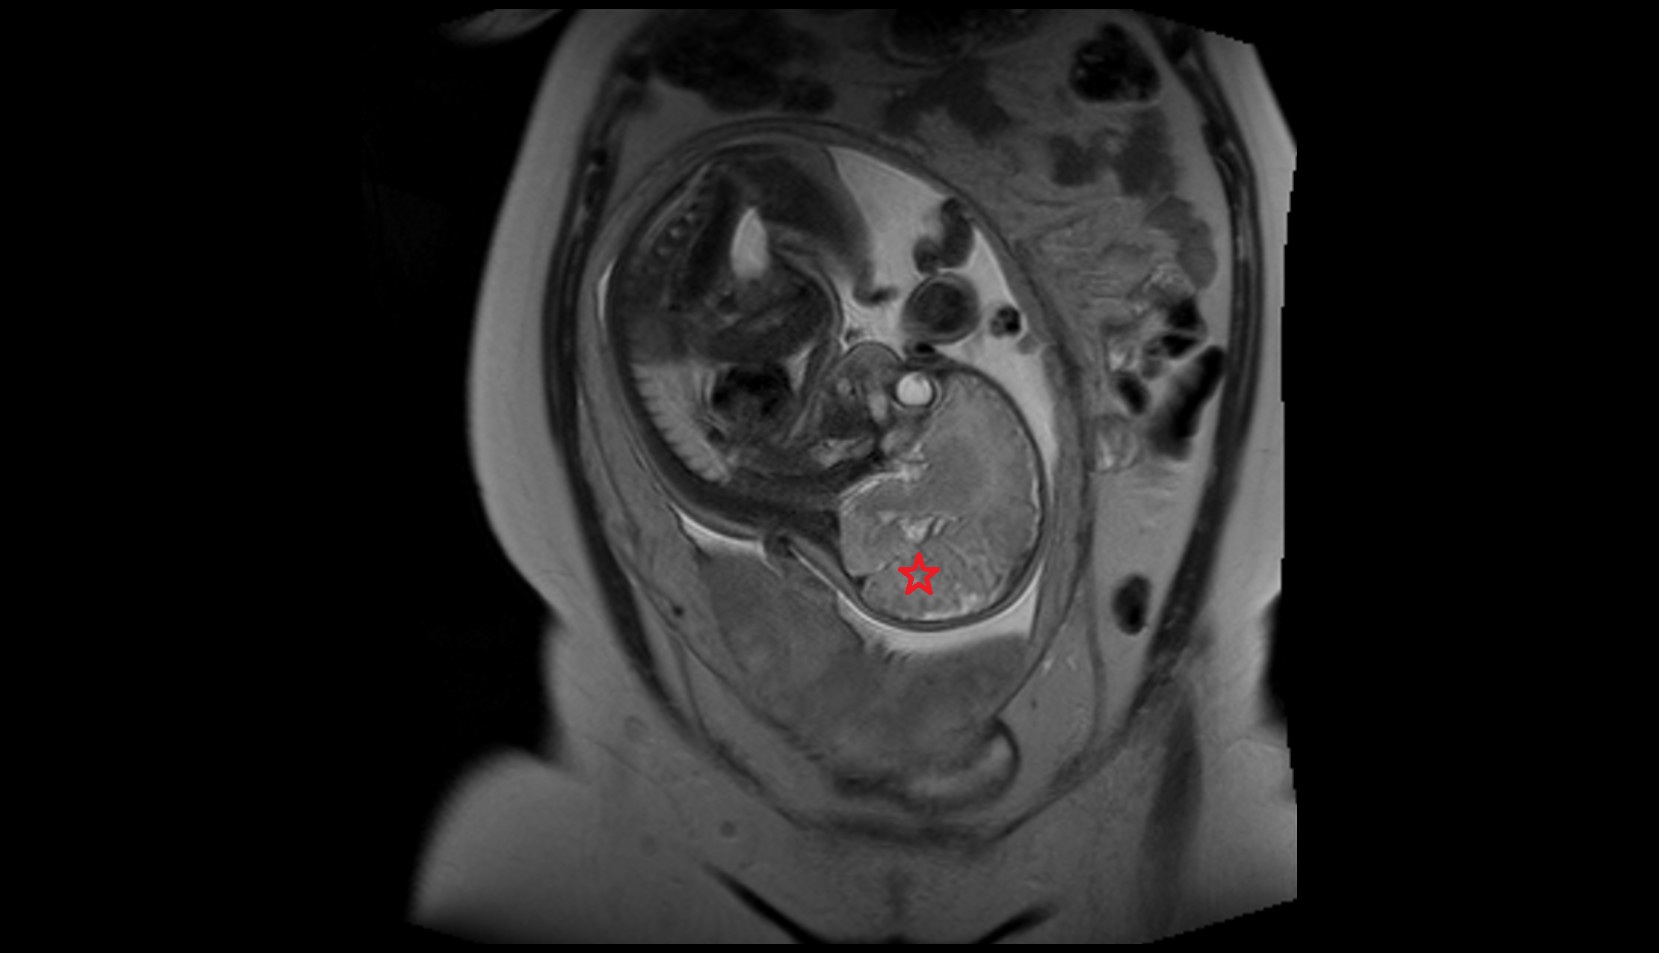

- Placenta

- Uterus (pregnancy)

- Amniotic fluid

- Umbilical cord

- Urinary Bladder in Pregnancy

- Cervix in Pregnancy

- Fetal brain

- Fetal caudate nucleus

- Fetal thalamus

- Fetal pons

- Fetal cerebellum